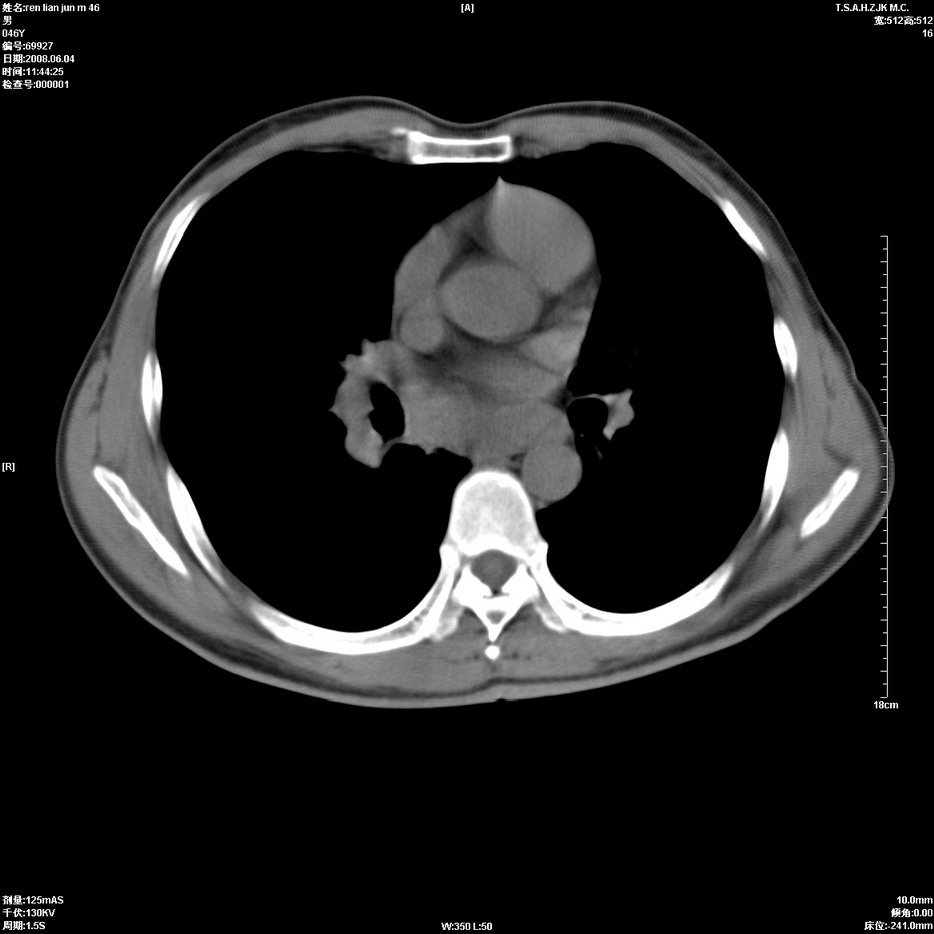

以下是引用qiu999在2008-6-5 17:14:00的发言:[br]考虑右肺中心型肺癌.颅内应做增强检查.

以下是引用形影不离在2008-6-5 19:18:00的发言:[br]右肺中心型肺癌并纵隔及左侧腋窝淋巴结转移,颅内应做增强检查。

以下是引用杀毒软件在2008-6-5 18:33:00的发言:[br]支持考虑右肺中心型肺癌,颅内病变是不是转移,不好说